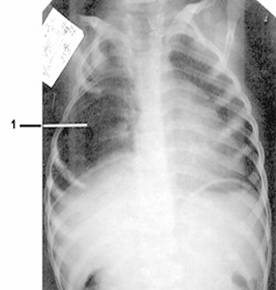

Рис. 1. Фото и рентгенограмма грудной клетки больной С. 4 лет с синдромом Поланда справа.

1 - гипоплазия 3 и 4 ребер справа.